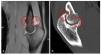

- Diagnóstico radiológico estándar: radiografías del codo en dos planos (fig.3).

Fig. 3 a, b) Vista general sobre el diagnóstico radiológico preoperatorio. En la radiografía estándar de la articulación del codo se observan cambios óseos, incongruencia articular, presencia de osteofitos y cuerpos libres articulares.

- Diagnóstico radiológico ampliado en caso de dudas especiales: tomografía por resonancia magnética, por ejemplo, para comprobar la presencia de cuerpos libres articulares (fig. 4a).

- Tomografía computarizada, por ejemplo, para la valoración de las superficies articulares y la localización de osteofitos (fig. 4b).

Fig. 4 a) En la imagen de la RMI se observan osteofitos en la zona del húmero anterior. b) El control mediante TAC muestra la magnitud y la localización de las formaciones osteofíticas.